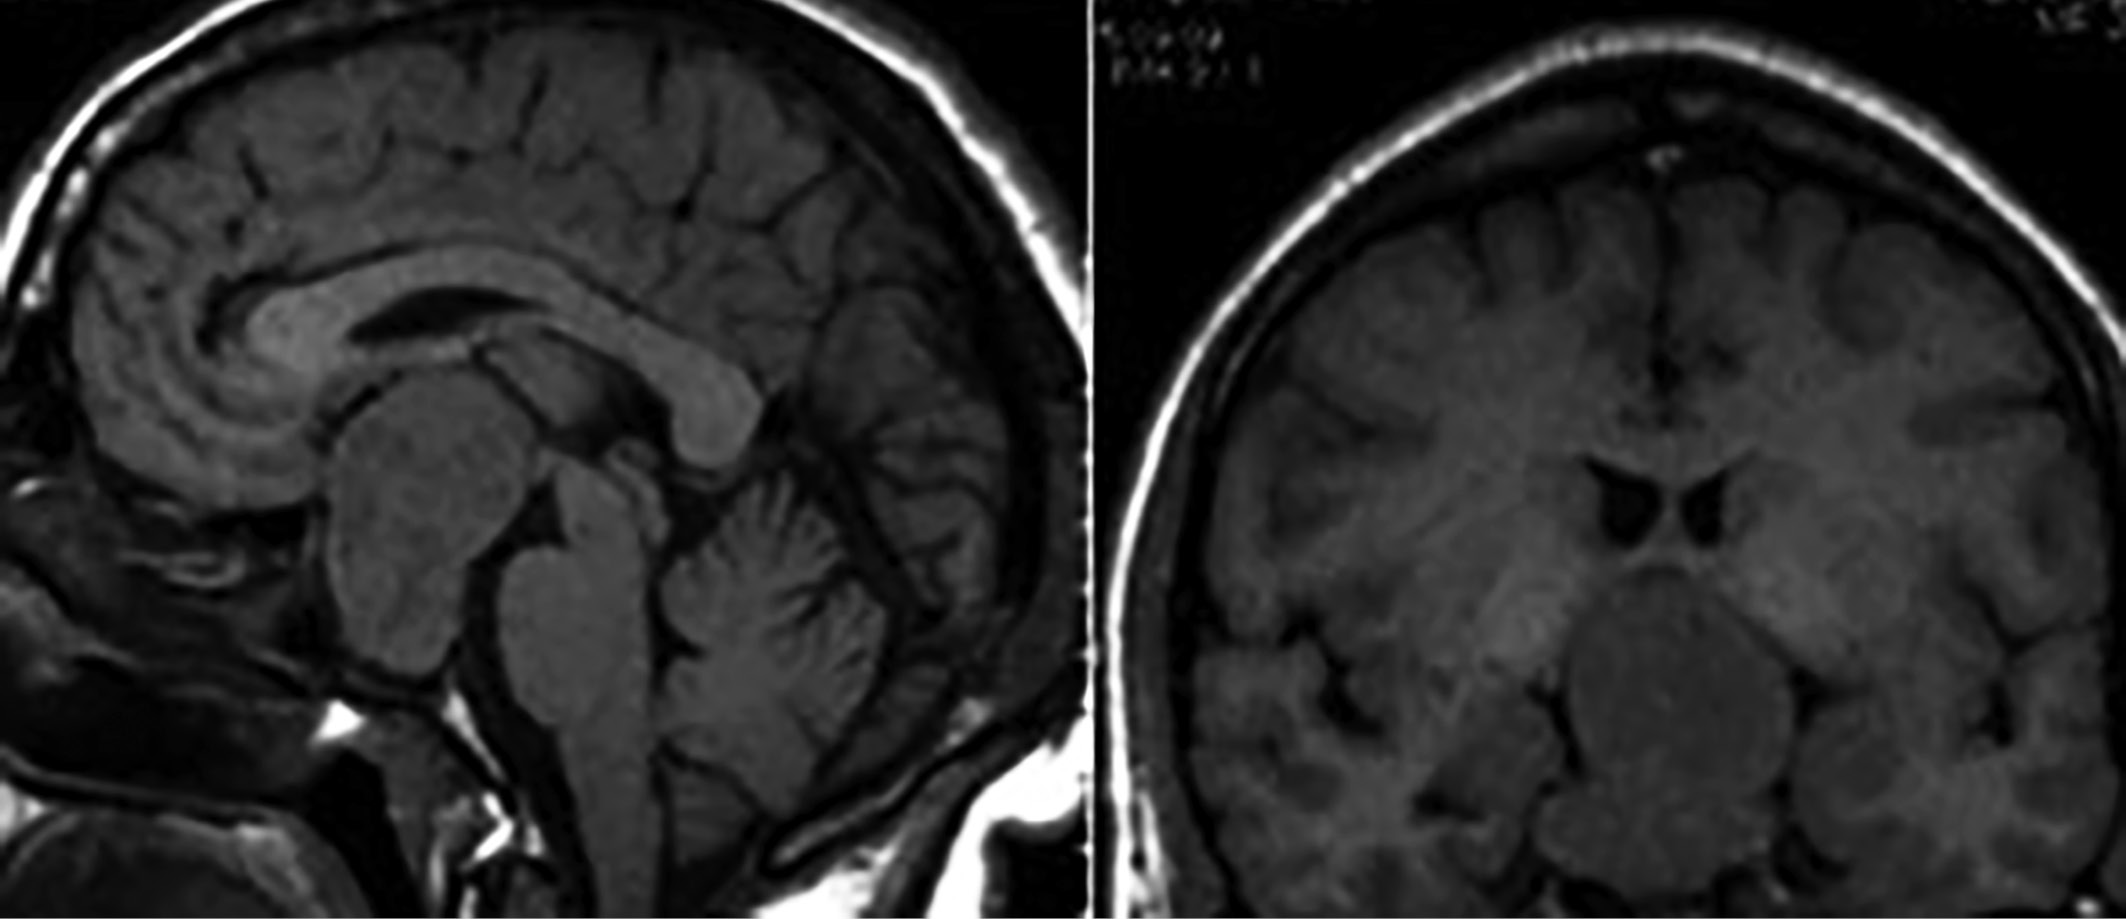

Для макроаденом (размер опухоли >1 см) часто характерен экстраселлярный рост. Опухоль может иметь супраселлярный, инфраселлярный, ретроселлярный, антеселлярный, латероселлярный рост и их сочетания. МРТ позволяет определить взаимоотношение опухоли с окружающими структурами: зрительными нервами, хиазмой, кавернозными синусами, ВСА, дном третьего желудочка, что важно при планировании хирургических доступов. Большинство макроаденом гипофиза имеют гипоинтенсивный сигнал в Т1-режиме и гиперинтенсивный сигнал в Т2-взвешенном режиме (рис. 9, 10). Кроме того, они могут иметь как гомогенную, так и гетерогенную структуру, а также содержать кистозный компонент. Введение контрастного вещества помогает дифференцировать ткань опухоли, для которой характерно менее интенсивное накопление контрастного вещества, от нормальной ткани гипофиза. В случаях больших аденом ткань гипофиза бывает настолько сдавлена, что может не определяться на МРТ.

Рисунок 9. Эндо-супра-инфра-латероселлярная соматотропинома. На сагиттальных (А) и фронтальных (Б) МР-томограммах в Т1-взвешенном режиме выявляется гипоинтенсивная опухоль с ростом в пазуху клиновидной кости, супраселлярно с компрессией хиазмы зрительных нервов, латероселлярно — в левый кавернозный синус с обрастанием сифона ВСА и сдавлением медиальных отделов височной доли.

Рисунок 10. Эндо-супра-инфра-латероселлярная соматотропинома. На сагиттальных (А) и фронтальных (Б) МР-томограммах в Т1-взвешенном режиме выявляется гипоинтенсивная опухоль с ростом в пазуху клиновидной кости, супраселлярно с компрессией дна 3-го желудочка, латероселлярно — в правый кавернозный синус.